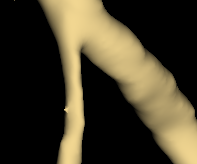

We hereby present a full synthetic model, able to mimic the various constituents of the cerebral vascular tree: the cerebral arteries, the bifurcations and the intracranial aneurysms. By building this model, our goal was to provide a substantial dataset of brain arteries which could be used by a 3D Convolutional Neural Network (CNN) to either segment or detect/recognize various vascular diseases (such as artery dissection/thrombosis) or even some portions of the cerebral vasculature, such as the bifurcations or aneurysms. In this study, we will particularly focus on Intra-Cranial Aneurysm (ICA) detection and segmentation. The cerebral aneurysms most often occur on a particular structure of the vascular tree named the Circle of Willis. Various studies have been conducted to detect and monitor the ICAs and those based on Deep Learning (DL) achieve the best performances. Specifically, in this work, we propose a full synthetic 3D model able to mimic the brain vasculature as acquired by Magnetic Resonance Angiography (MRA), and more particularly the Time Of Flight (TOF) principle. Among the various MRI modalities, the MRA-TOF allows to have a relatively good rendering of the blood vessels and is non-invasive (no contrast liquid injection). Our model has been designed to simultaneously mimic the arteries geometry, the ICA shape and the background noise. The geometry of the vascular tree is modeled thanks to an interpolation with 3D Spline functions, and the statistical properties of the background MRI noise is collected from MRA acquisitions and reproduced within the model. In this work, we thoroughly describe the synthetic vasculature model, we build up a neural network designed for ICA segmentation and detection, and finally, we carry out an in-depth evaluation of the performance gap gained thanks to the synthetic model data augmentation.